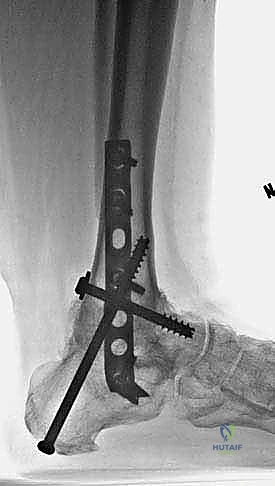

التحام مفصل الكاحل والكعب بالصفيحة النصلية هو إجراء جراحي حيوي يهدف إلى تثبيت وتصحيح التشوهات الشديدة في القدم والكاحل، خاصةً الناتجة عن اعتلال شاركو العصبي. يتضمن دمج عظمي قصبة الساق والكعب باستخدام صفيحة نصلية لتوفير تثبيت صلب وفوري، مما يساعد على استعادة القدرة على المشي وتجنب البتر.

يُعد إجراء "التحام مفصل الكاحل والكعب بالصفيحة النصلية" (Tibiocalcaneal Arthrodesis Using Blade Plate Fixation) واحداً من أعقد وأهم التدخلات الجراحية لإنقاذ الأطراف في طب جراحة العظام الحديث. يهدف هذا الإجراء الحيوي إلى حماية الأطراف السفلية من خطر البتر الحتمي لدى المرضى الذين يعانون من تشوهات شديدة ومعقدة في القدم والكاحل. وتحديداً، تلك الحالات الناتجة عن اعتلال "شاركو" العصبي المفصلي (Charcot Neuroarthropathy) المتقدم، أو الفشل السابق لجراحات الكاحل، أو التهابات المفاصل الروماتويدية الشديدة.

تاريخياً، تم استخدام المسامير النخاعية (Intramedullary Nails) أو البراغي العادية لدمج الكاحل. ولكن في الحالات شديدة التعقيد، حيث تكون عظمة الكاحل (Talus) مدمرة تماماً ويجب استئصالها (Talectomy)، تصبح المسألة هي كيفية تثبيت قصبة الساق مباشرة بعظمة الكعب (Tibiocalcaneal Fusion).

هنا تبرز الصفيحة النصلية (Blade Plate) كالحل الذهبي. تتميز هذه الصفيحة بوجود "نصل" صلب يتم إدخاله بقوة داخل عظمة الكعب، بينما يتم تثبيت الجزء الطولي من الصفيحة على عظمة قصبة الساق بالبراغي. هذا التصميم الهندسي يوفر مقاومة هائلة لقوى الانحناء والدوران، مما يضمن ثباتاً فورياً يسمح للعظام بالالتحام بشكل مثالي.

5. إدخال وتثبيت الصفيحة النصلية (Blade Plate)

هنا تكمن المهارة الجراحية الفائقة. يتم تشكيل مجرى دقيق داخل عظمة الكعب باستخدام إزميل خاص، ثم يتم طرق "نصل" الصفيحة المعدنية بحذر شديد داخل عظمة الكعب لضمان أقصى درجات الثبات.

6. التثبيت النهائي بالبراغي (Screw Fixation)

بعد التأكد من الموضع المثالي للصفيحة والنصل، يتم تثبيت الجزء العلوي من الصفيحة على عظمة قصبة الساق باستخدام براغي قشرية (Cortical Screws) قوية. يتم وضع العظام تحت ضغط ميكانيكي (Compression) لتحفيز الخلايا العظمية على الالتحام السريع.